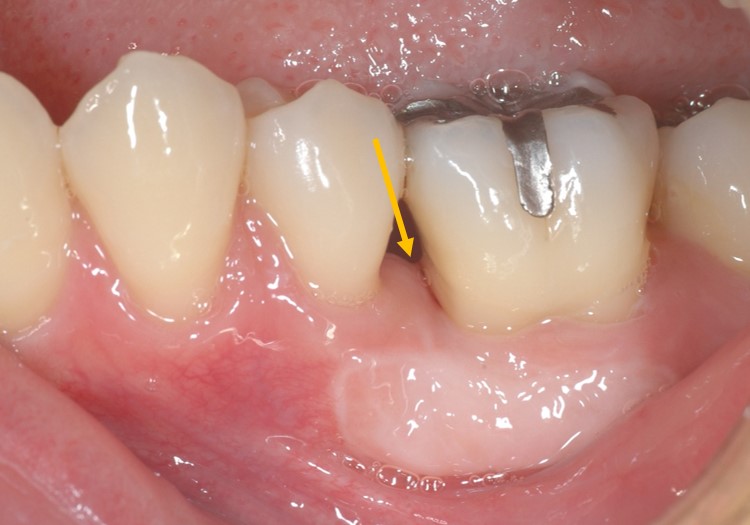

下写真は術前です。オレンジ矢印部分に6mmの歯周ポケットが存在します。